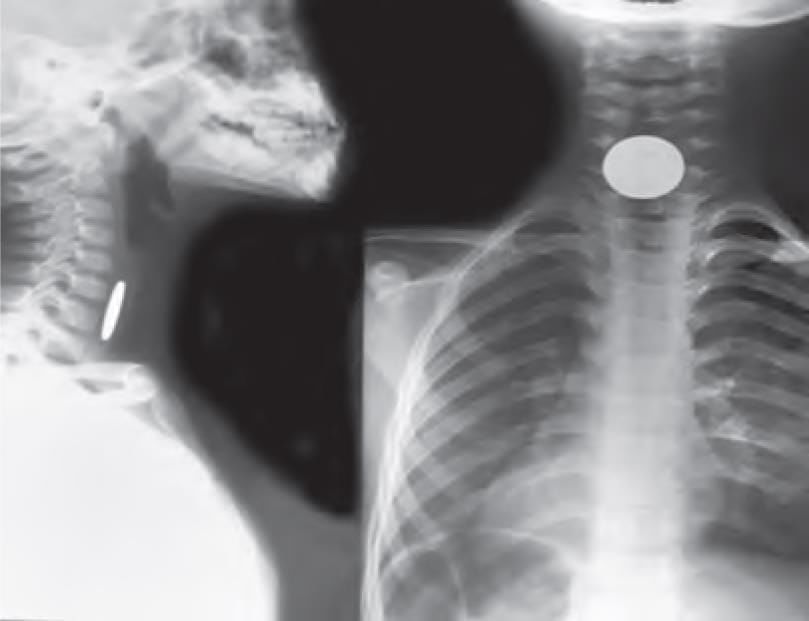

A 9-year-old male baby was brought to emergency by the mother with difficulty in swallowing for past few hours and a history of playing unsupervised. X-ray was taken. Identify the location of foreign body. (NEET-PG 2021)

Detailed Solution for Test: Anatomy - 3 - Question 22

The foreign object seems to be a coin, located just anterior to the vertebrae (where the oesophagus is situated). Additionally, there is a tracheal air shadow noted in front of the coin. This indicates that it is a coin lodged in the oesophagus. This is further supported by the patient presenting somewhat late with a complaint of difficulty in swallowing (indicating a foreign body in the gut tube) rather than in an acute emergency due to difficulty in breathing (suggesting a foreign body in the respiratory tube).